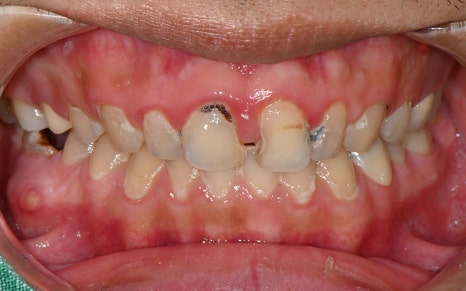

어느정도 치료를 진행한 후의 모습인데요.

무엇보다도 눈에 띄는 변화는

앞니의 심미 복원입니다.

치료 전 사진을 보면 웃음을 짓기 어려울 정도로

앞니에 큰 충치와 손상이 있었고,

중간중간 레진으로 채워진 부분이

심미적으로도 큰 스트레스였다고 하셨습니다.